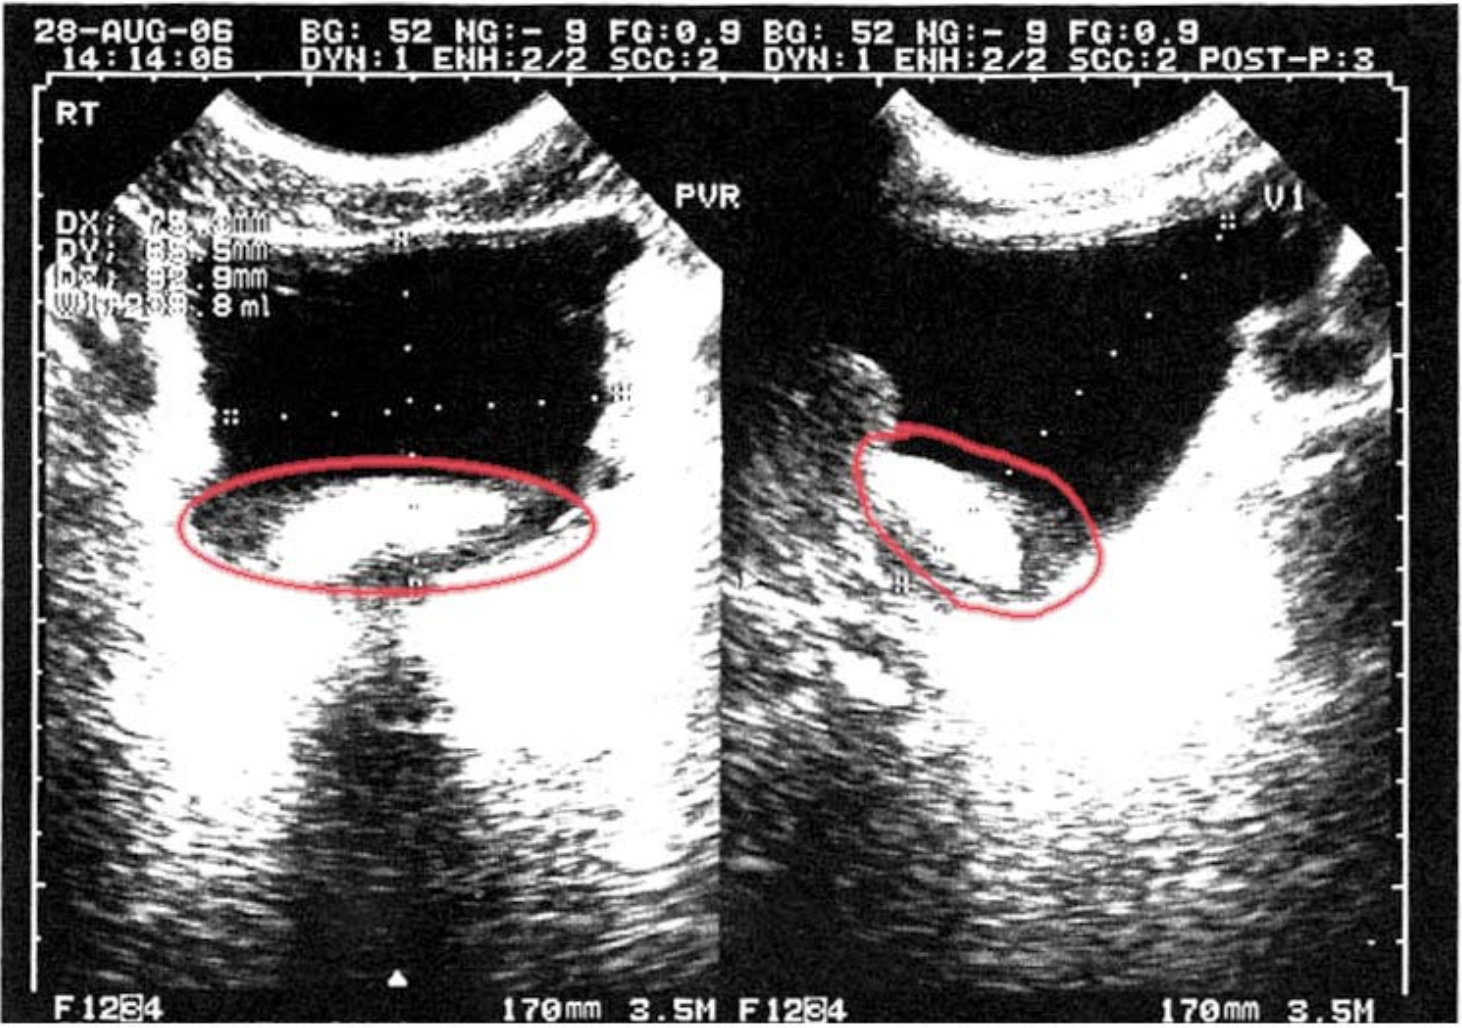

Two and a half days after pain began and increased to cause headaches, I watched the ultrasound screen reveal a large mass. The mass was blocking the outflow of urination to my urethra.

The urologist looked extremely concerned. I took that as normal terrorist tactics. I got ready to receive alarming news that I had a huge tumor that require immediate surgery. Instead, he said, "That is the largest bladder stone I have every seen; in experience and literature. You have not had pain before only 3 days ago?" I had not.

Naturally dissolving a stone that size could take months and my next lecture tour was to begin in 2 weeks. The urologist explained that he would insert 3 tubes: a laser to blast the stone, a camera to accomplish that and a water tube for flushing stone debris. I imagined a tube holding the three tubes to be inserted in my penis, up my urethra to my bladder to be about 1/4 inch in diameter; ouch. The urologist said that the entire procedure, once it began would take about 45 minutes. I decided I would undergo non-surgical removal of my one massive stone.

When I arrived home, I called the urologist's office and asked what happened during procedure. She transferred the call to the urologist. He told me that it was not only outrageously large but hard, almost like metal. It took him over 1 hour 45 minutes to disintegrate the stone. Its core, he said, was the size of a large marble and black like steel.

He stated that to be that dense and large, it had to have formed over several decades. It was the most gruesome task he had every performed. He had to increase the intensity of the laser and still ensure that he did not tear/burn my bladder. He said that he sent some of the fragments and a bladder-scrape to the lab to ensure no cancer resulted.